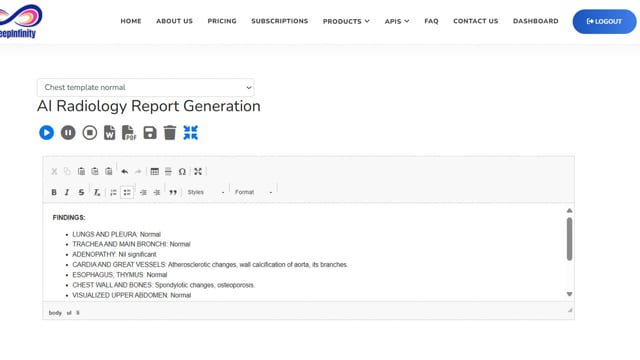

DeepInfinity.AI specializes in using advanced Generative AI and ML technologies to transform healthcare diagnostics and patient care. Our platform applies generative AI models for deep and accurate analysis of medical data, offering a range of predictive and diagnostic tools. These tools are designed to support healthcare professionals in making faster, more accurate diagnoses, thereby enhancing the overall quality of patient care. DeepInfinity.AI uses the advanced Generative AI technology to help Doctors, Hospitals and Diagnostic Centers & Labs etc.